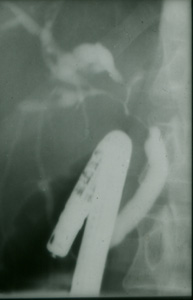

Slide Museum: Gall Bladder & Bile Duct etc : ERCP showing bile duct structures